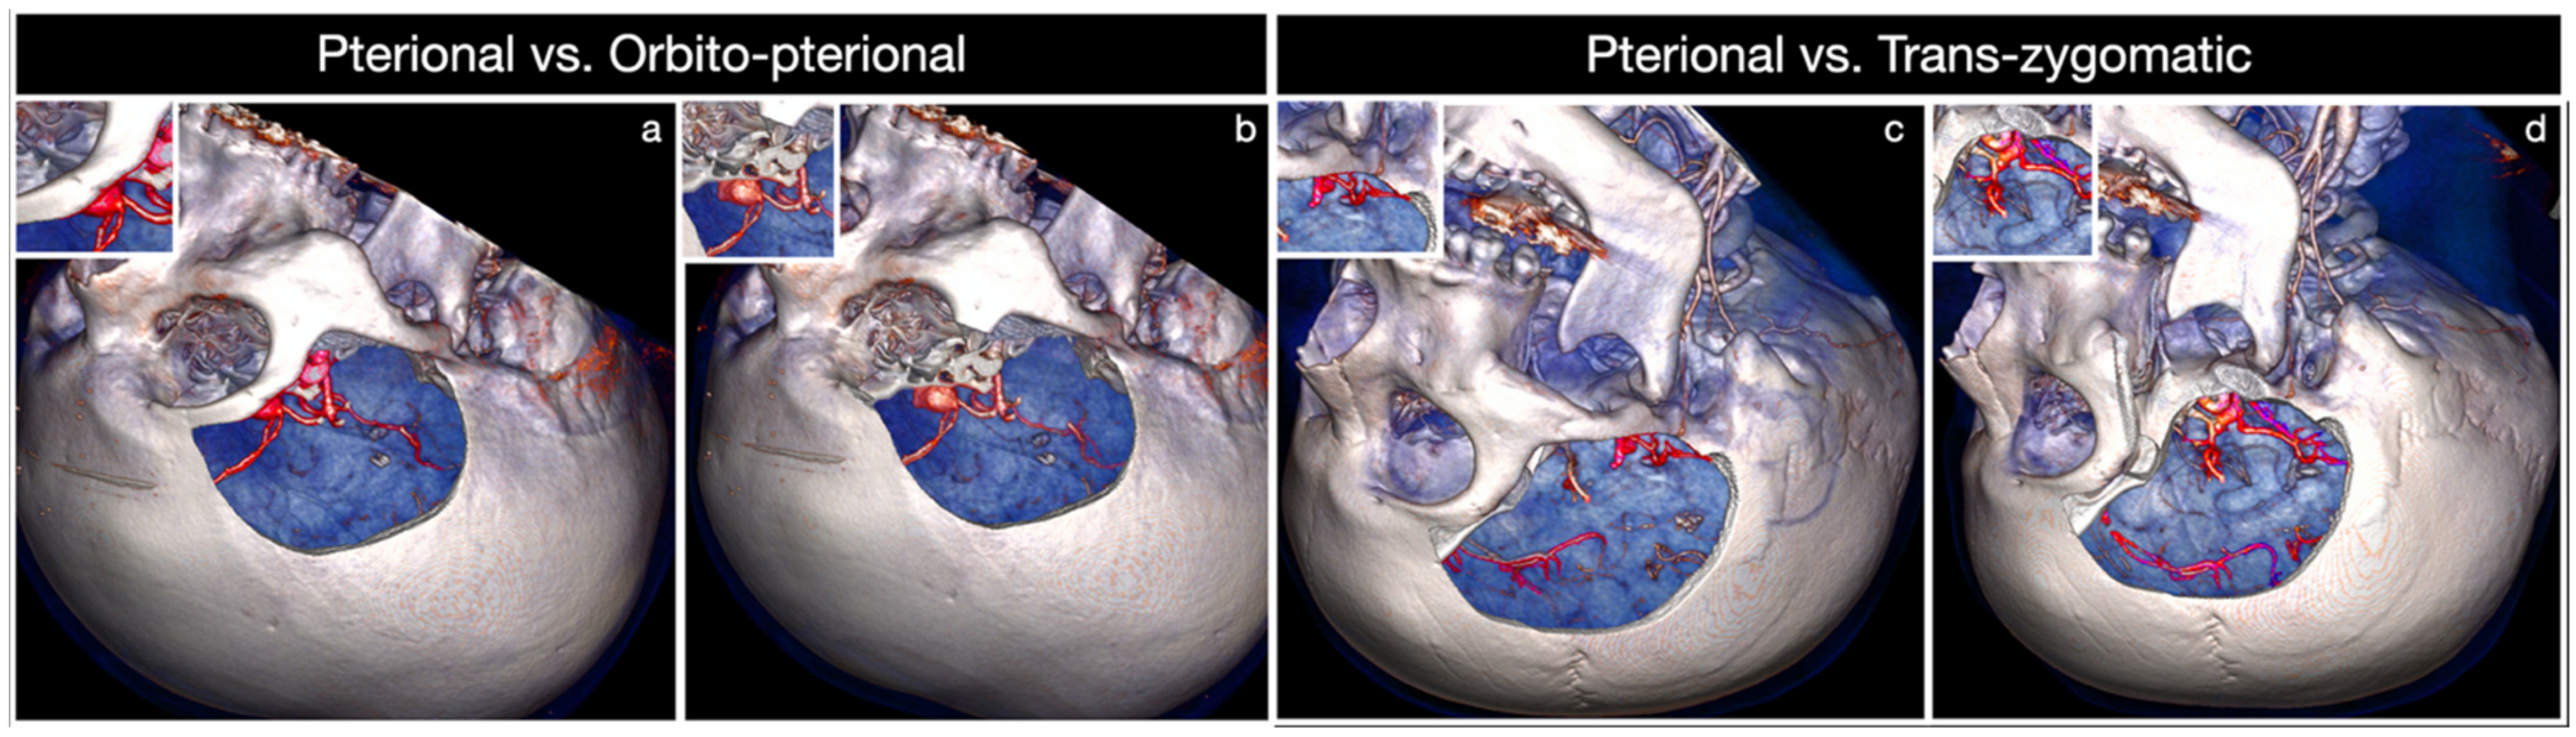

4. Discussion

4.2. Clinical Algorithm